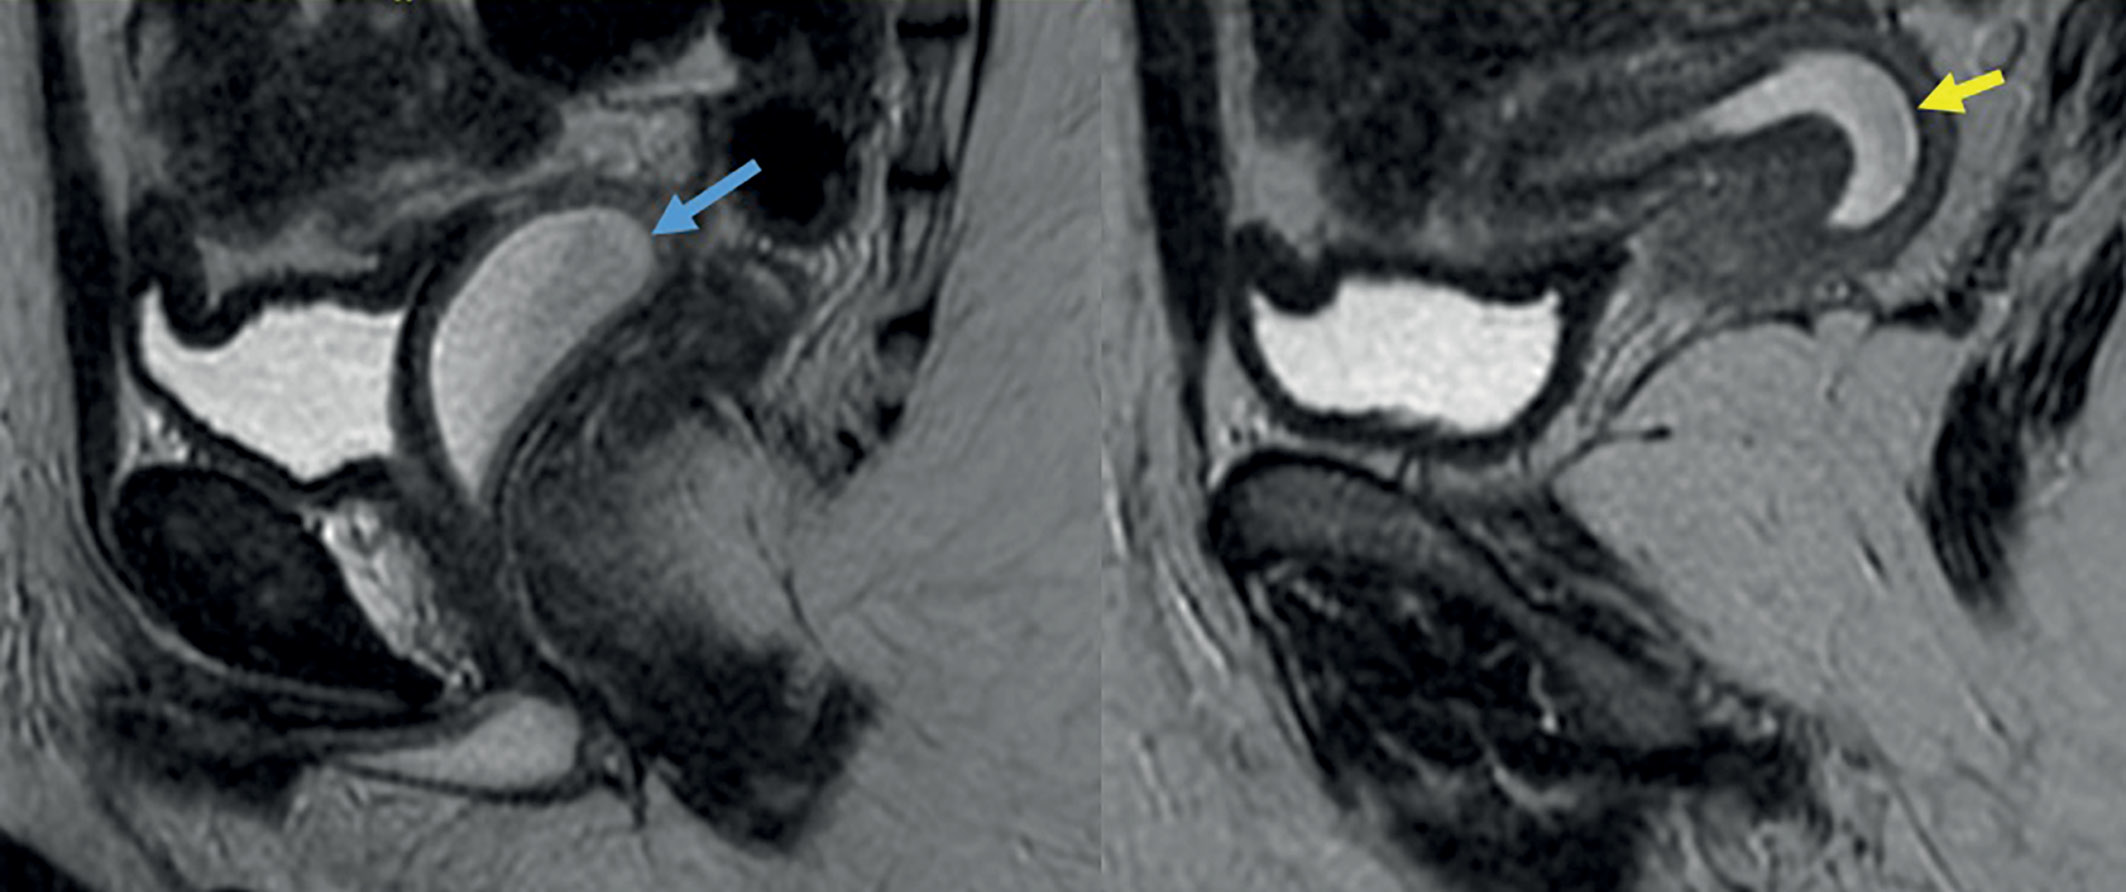

Рисунок 2. Серия МРТ-срезов малого таза у девочки 12 лет с сольтеряющей формой врожденной дисфункции коры надпочечников.

Диагноз поставлен при рождении на основании высокого уровня 17-гидроксипрогестерона, женского кариотипа и вирилизации наружных половых органов 5-й степени. В раннем возрасте выполнены пластика гипертрофированного клитора и синусотомия. В возрасте 12 лет в связи с макрогематурией выявлены признаки гематокольпоса (синяя стрелка) и гематометры (желтая стрелка), подтвержденные МРТ-исследованием. Благодаря оперативным действиям эндокринологов по месту жительства и родителей девочку оперативно госпитализировали и прооперировали в институте эндокринологии. В связи с высокой формой уретро-вагинального свища и недостаточной эстрогенизацией и поэтому высоким риском осложнений решено отказаться от разобщающей интроитопластики в пользу проведения синусовагинотомии. Клинический пример демонстрирует неэффективность синусотомии, выполненной в допубертатном периоде, — несмотря на рассечение общего мочеполового канала, было получено осложнение со стороны половых путей в виде гематокольпоса и гематометры, причиной которого был узкий вход во влагалище.